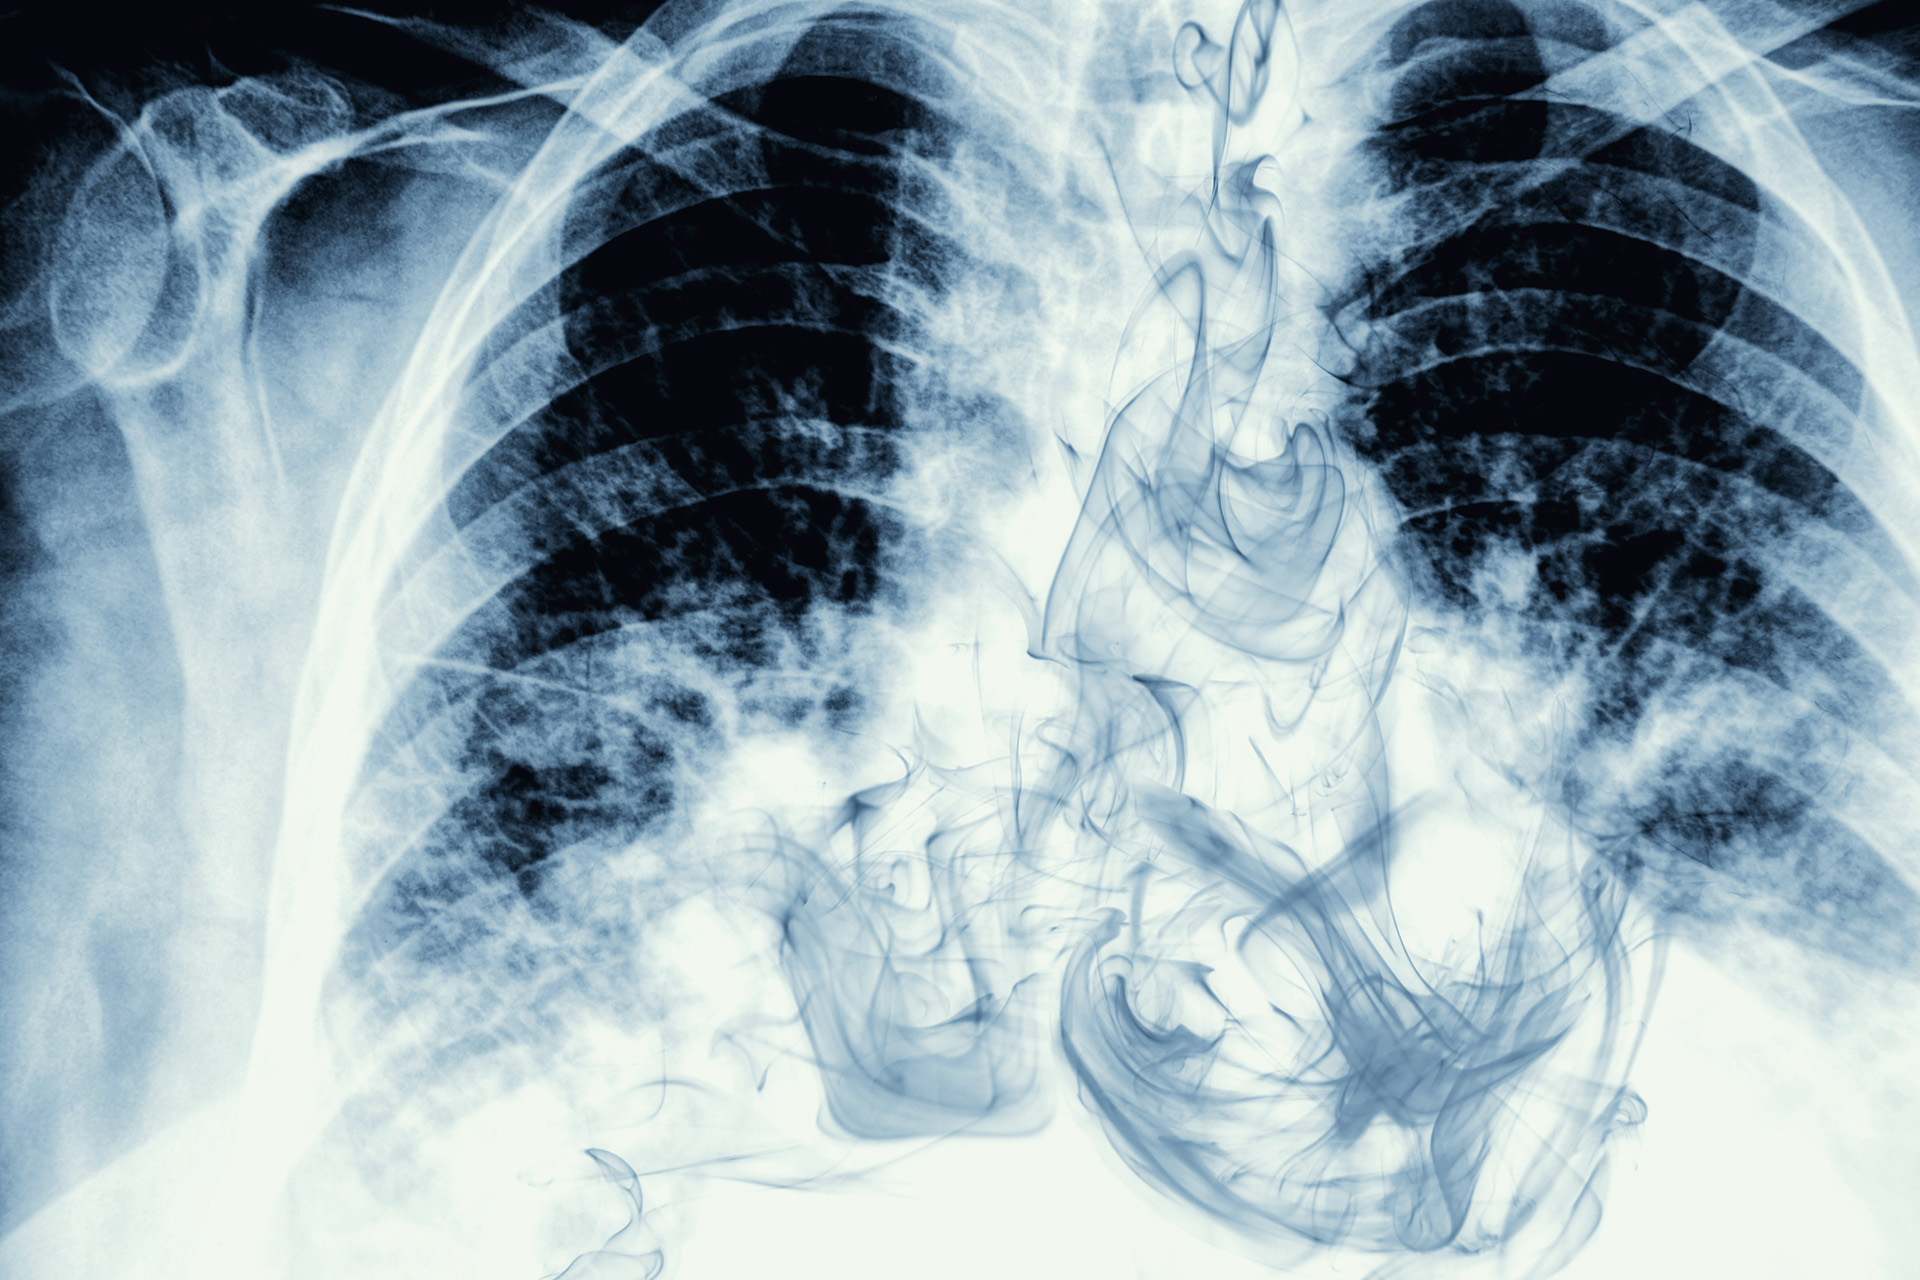

На КТ лёгкие вейпера могут выглядеть как при вирусной пневмонии или COVID-19: часто видны зоны «матового стекла» и уплотнения. Без признания пациентом факта парения врач может начать лечить несуществующую инфекцию, пропуская реальную причину — химическое воспаление от вейпинга. Хроническое воспаление от вейпов способно имитировать на снимках не только пневмонию, свойственную COVID-19, но и другие интерстициальные заболевания легких, включая рак. Это требует применения дополнительных диагностических инструментов, которые не всегда необходимы при стандартных случаях. Курение обычных сигарет дает схожие эффекты на изображениях, но в меньшей степени, а вот стики занимают промежуточное положение.